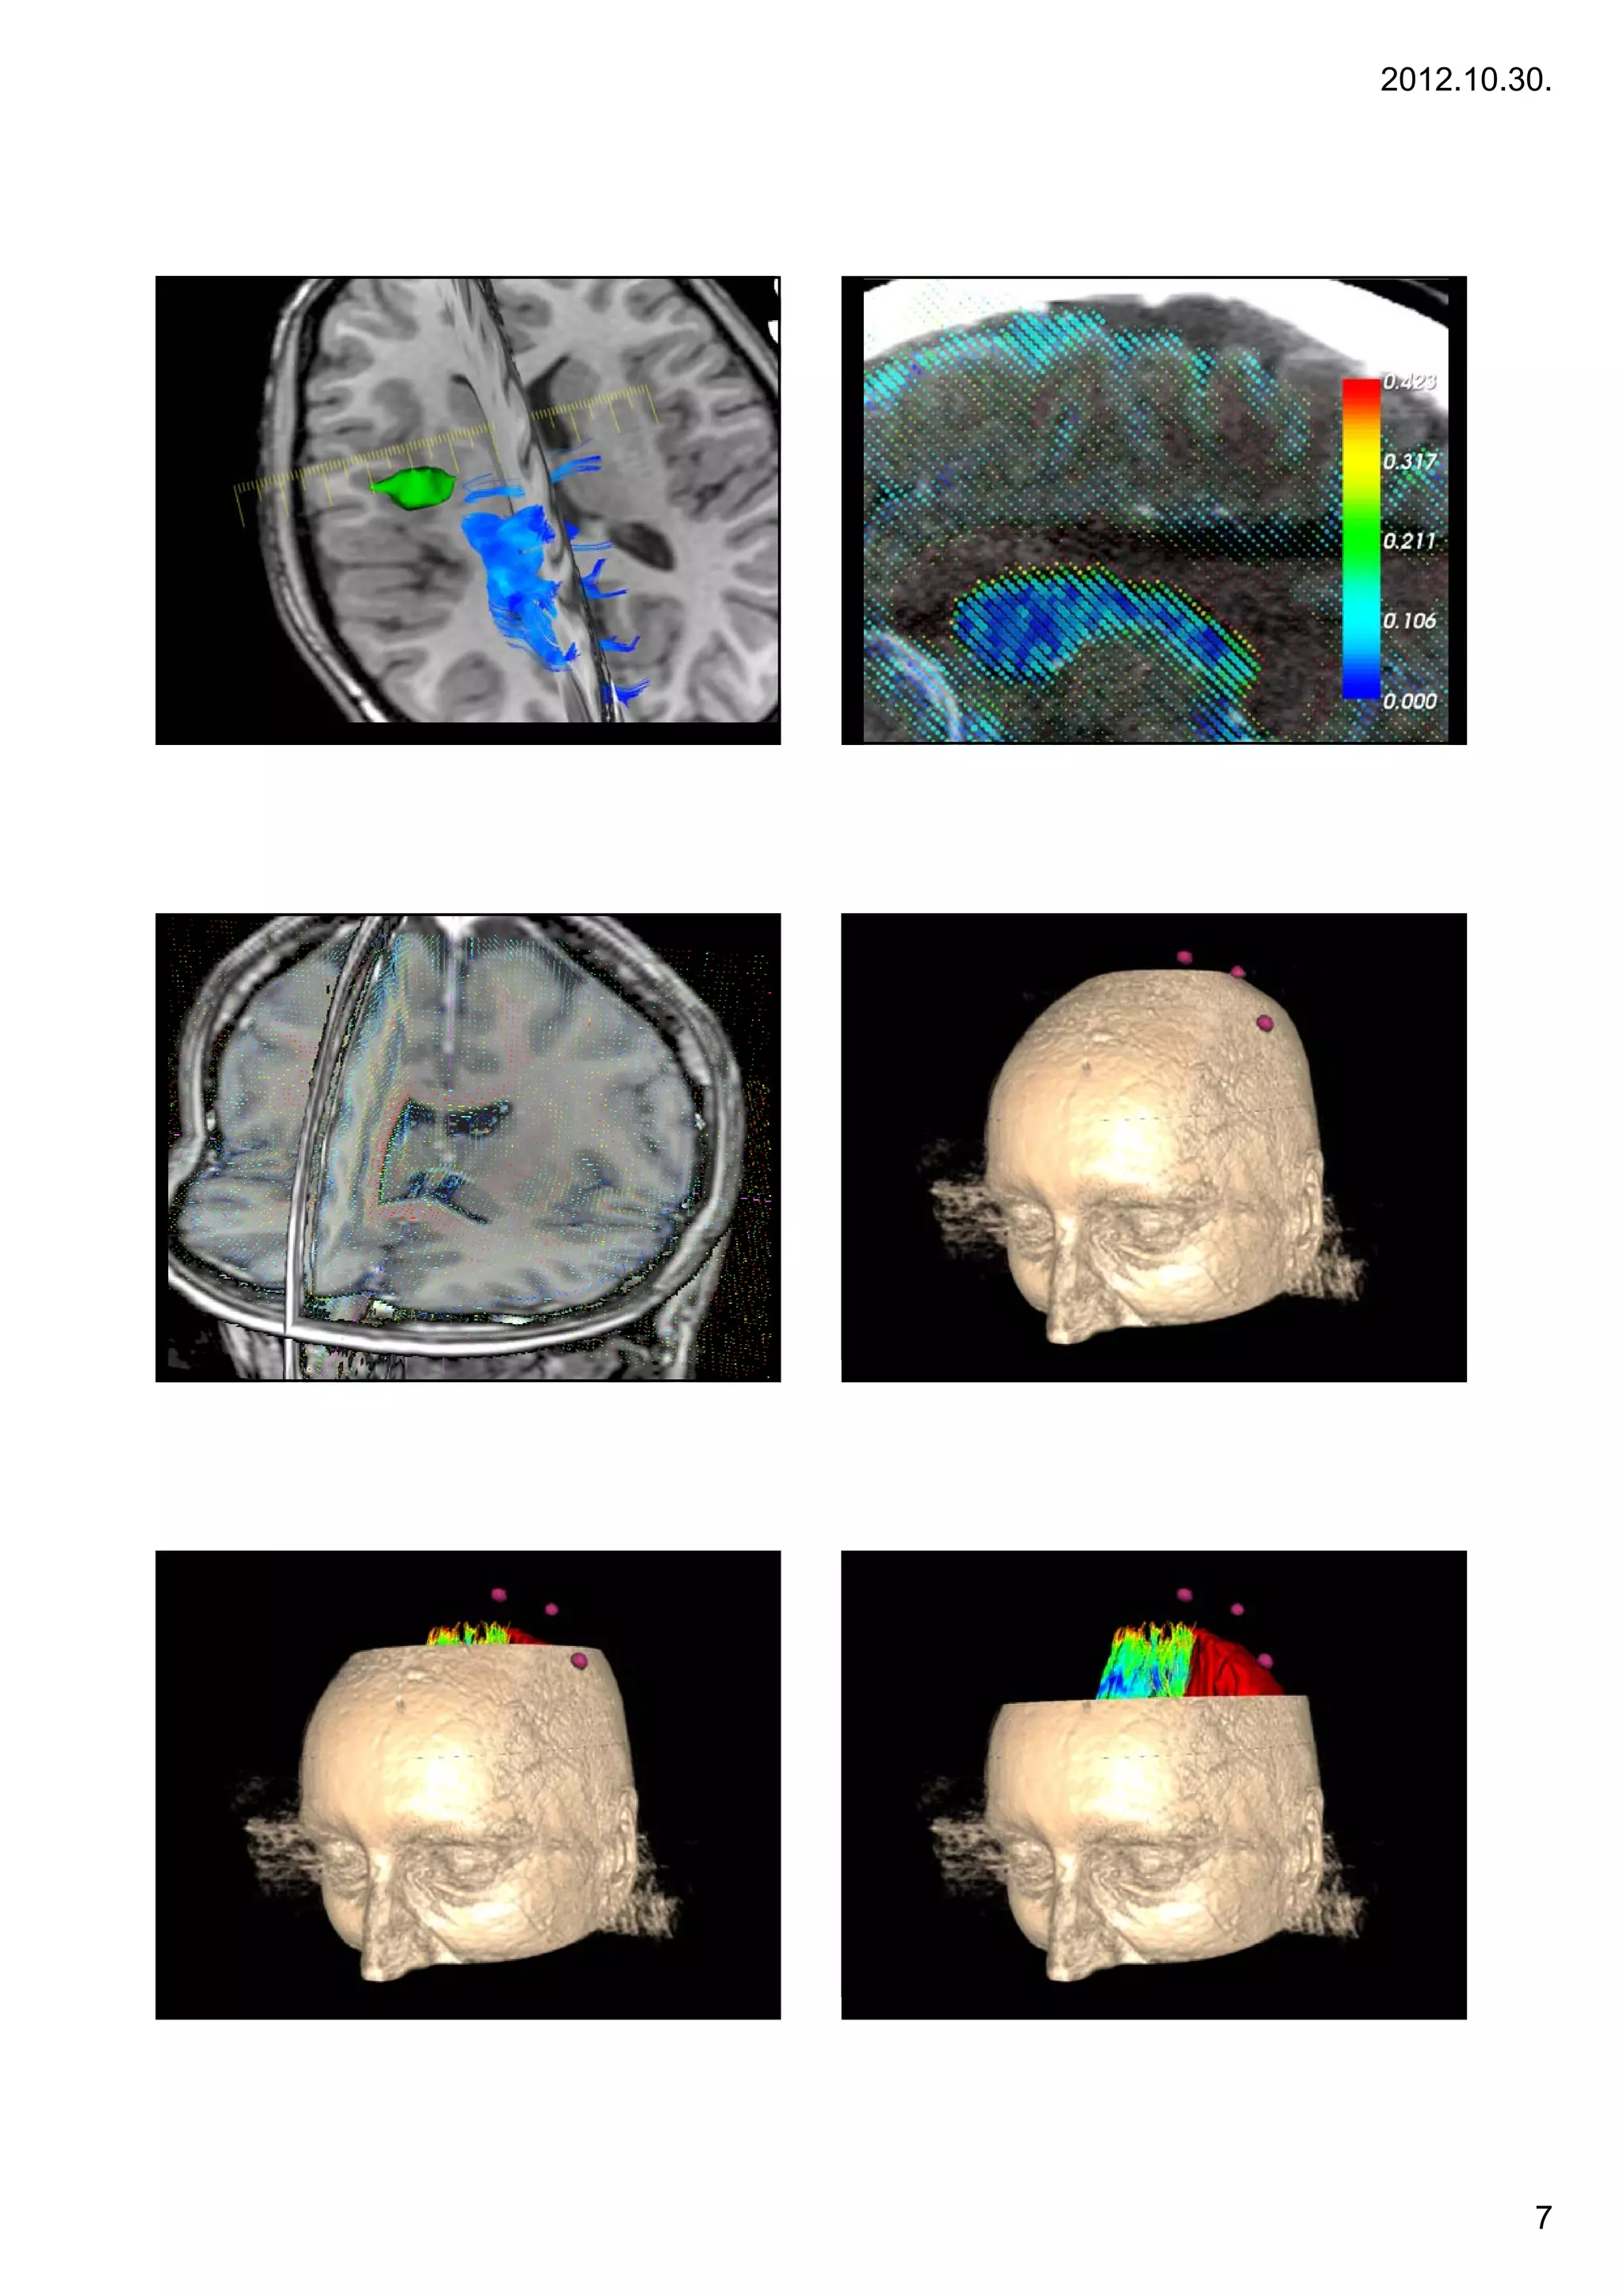

Information from                                                        Diffusion information:

13          conventional MR images                                        14        DTI and fibertracking

•   Displaying white matter tracts

•   Tumor adjacent tracts

•   Diffusion mapping

•   Characterizing pathologies